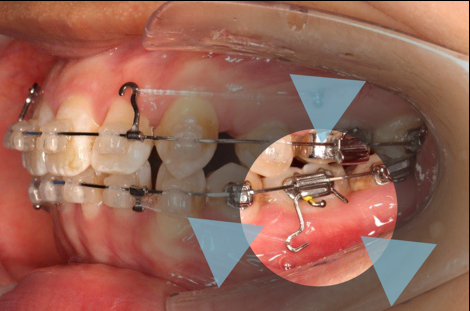

上颌矫治的生物力学

上颌使用高位种植钉及长牵引钩,配合尖牙近远中的v-bend,上颌前牙的牙齿移动方式是整体往上,往后内收。

下颌整平内收的生物力学

下前牙的压低+控制性倾斜移动内收,改善唇倾度,磨牙通过powerarm 直立,控根整体近中移动,使咬合高点的前移,整平下颌同时进行内收。